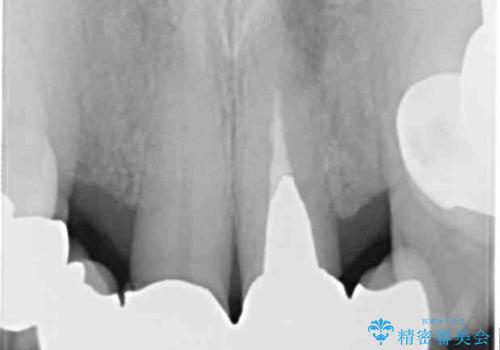

- ブリッジと歯肉の隙間にものが挟まったり空気が抜けたり、歯肉ラインの黒い縁が目立ってしまったりと、前歯のブリッジの作り直しを希望して来院された患者様です。

自然な仕上がりとするため、金属を使用しないオールセラミックブリッジにより補綴治療を行うこととしました。